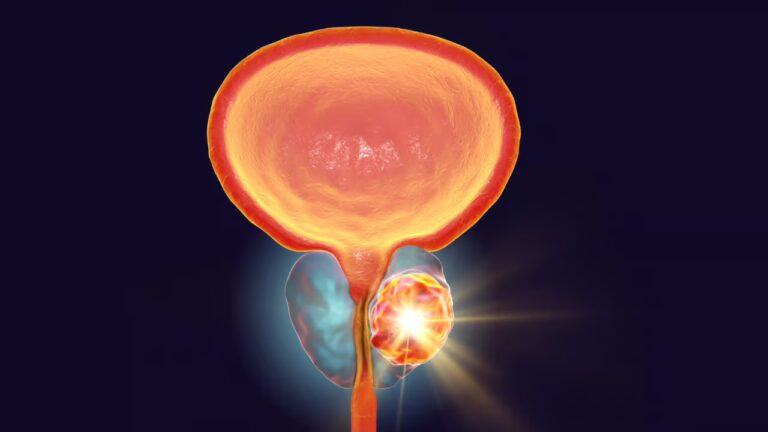

Maurice, 65 ans, souffre d’une tumeur maligne de la prostate localisée à haut taux de récidive, qui nécessite des séances de radiothérapie ainsi qu’une

hormonothérapie. Son médecin lui a prescrit du dégarelix, de l’abiratérone et de la prednisone.

Le cancer de la prostate est le cancer le plus fréquent chez l’homme en France (71 200 nouveaux cas estimés en 2011) et représente la troisième cause de décès par cancer masculin. Bien qu’il soit associé à un bon pronostic, avec une nette amélioration de la survie à cinq ans ces dernières décennies, il reste une pathologie lourde aux multiples implications thérapeutiques et humaines.

Cette formation vise à renforcer le rôle du pharmacien d’officine dans la prise en charge globale des patients atteints d’un cancer de la prostate. Elle aborde les aspects clés de la maladie : épidémiologie, diagnostic, traitements médicamenteux et non médicamenteux, ainsi que la gestion des effets indésirables.